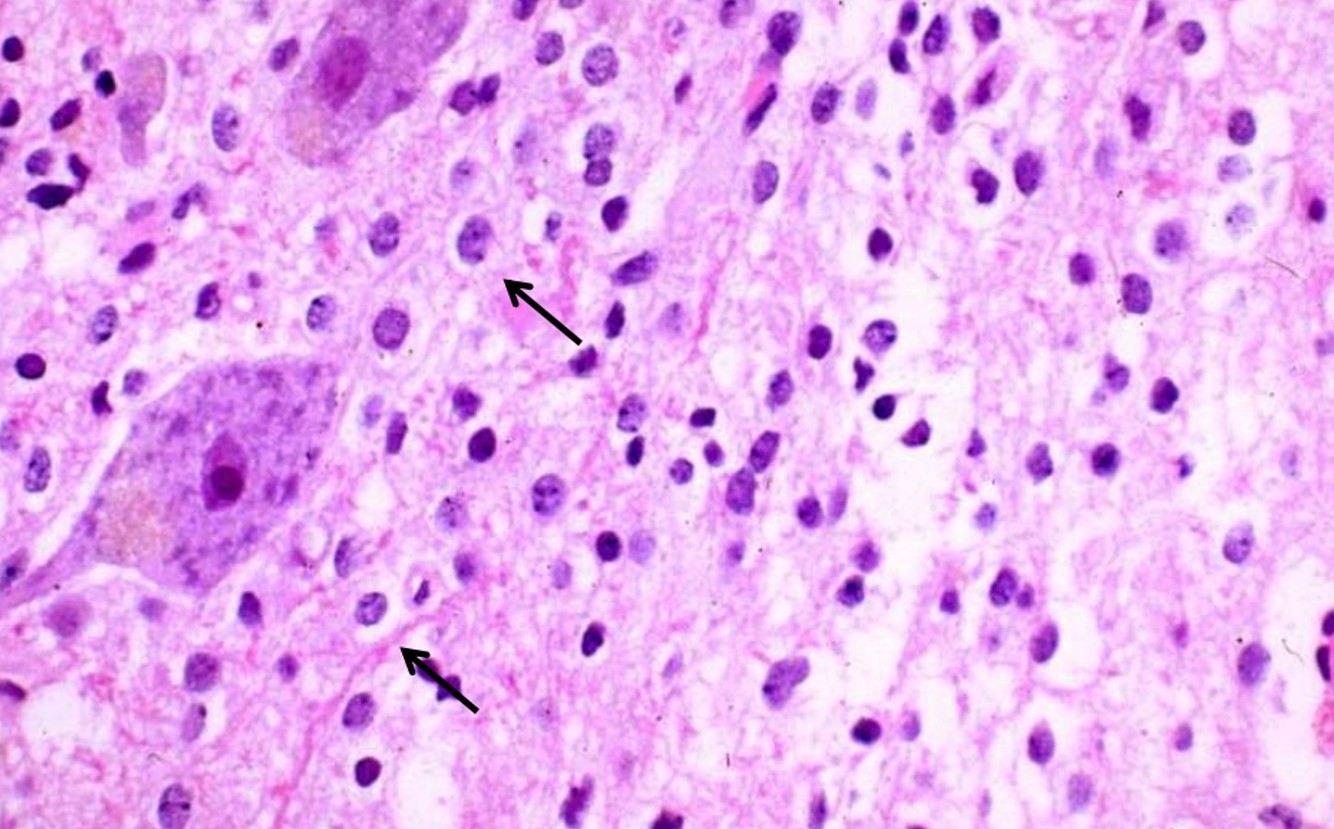

Gemistocytic astrocytoma

- p53 positive

- Prone to progress to anaplastic and GBM

Oligodendroglioma

- 5-15% of gliomas

- Age: 40 ~ 50 y/o, rare in children

- Restricted to supratentorial compartment

- Interval to anaplastic progression is longer relative to astrocytoma (range 9y, vs 4-5y for latter)

- 1p, 19q deletion, oligodendroglial ‘signature’; connotes chemosensitivity